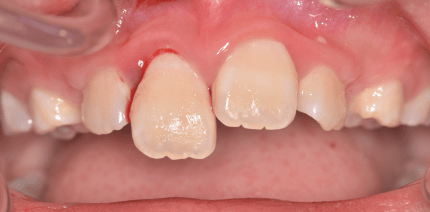

Das dentale Trauma stellt Zahnärztinnen und Zahnärzte in der Praxis immer wieder vor mehr oder weniger große Herausforderungen. Dies liegt...

Das dentale Trauma stellt Zahnärztinnen und Zahnärzte in der Praxis immer wieder vor mehr...

Im Bereich der Zahnheilkunde resultieren Traumata häufig in Verletzungen der Frontzähne. Aber nicht nur die Soforttherapie, auch Spätfolgen...

Im Bereich der Zahnheilkunde resultieren Traumata häufig in Verletzungen der Frontzähne....